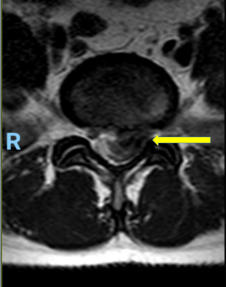

Hernia de disco lumbar extrusa L5 S1 (cortes axiales mostrando

gran compresión sobre la raíz nerviosa izquierda del segmento)

Hernia de disco lumbar extrusa L5 S1 (cortes axiales mostrando gran compresión sobre la raíz nerviosa izquierda del segmento)